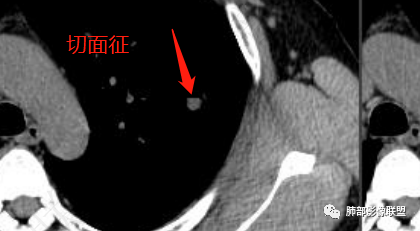

1、考虑恶性病变的征象:肚脐凹征、轻度分叶征、V征或支气管半进入征、远端局部阻塞性改变,以及递增性强化等征象,临床上半年结节有增大,腺癌可以考虑;

2、考虑良性结节:可见切面征,形态较为规则,整体类圆形改变,可考虑炎性假瘤,半年后无炎性纤维组织的收缩、尖角或桃尖征改变,尤其半年后体积增大的炎性病变,还是罕见。部分层面见血管贴边征,PSP可以考虑。